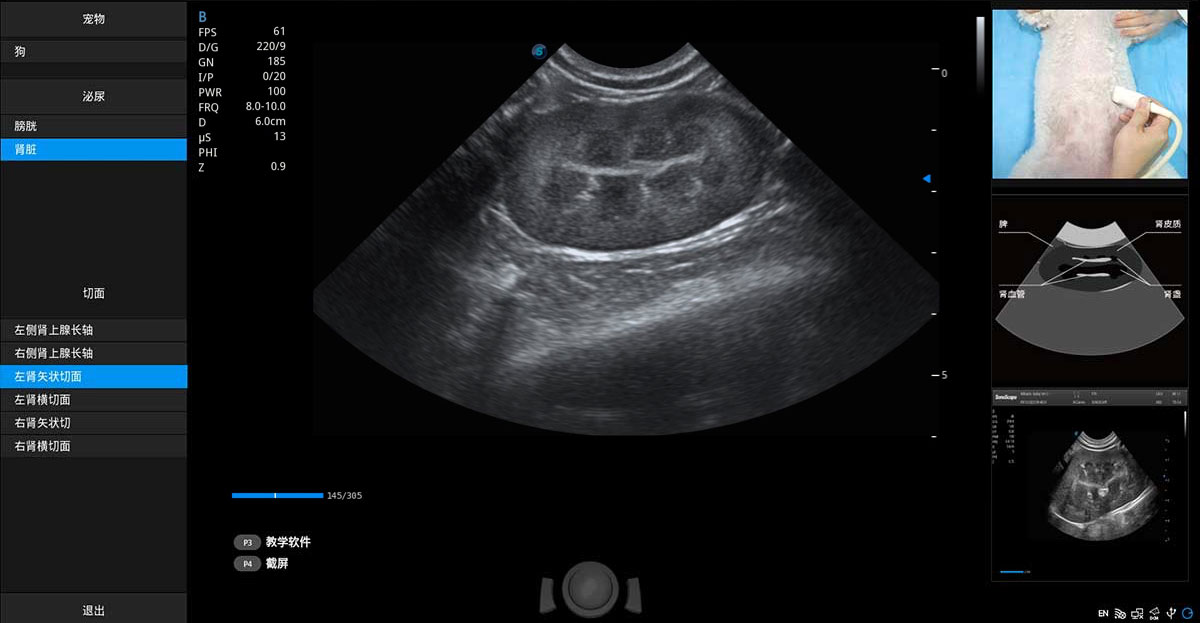

提供解剖示意圖、標(biāo)準(zhǔn)超聲圖像、掃查手法涂和操作者實(shí)時(shí)檢查圖像,指導(dǎo)操作者進(jìn)行標(biāo)準(zhǔn)切面的正確掃查。

ProPet 80 專為動(dòng)物醫(yī)生設(shè)計(jì),對(duì)不同的動(dòng)物體型和生理結(jié)構(gòu)作出了針對(duì)性的優(yōu)化。通過(guò)動(dòng)物影像專用軟件,可滿足個(gè)性化的應(yīng)用需求,幫助動(dòng)物醫(yī)生獲得更精確的診斷數(shù)據(jù)。

ProPet 80 全新的動(dòng)物超聲智能軟件和豐富的探頭群,為動(dòng)物醫(yī)生提供了高清晰度和精細(xì)分辨率的圖像,無(wú)論在寵物、馬科、畜牧還是實(shí)驗(yàn)室動(dòng)物等應(yīng)用中都可以輕松應(yīng)對(duì),為您的日常工作帶來(lái)滿意的體驗(yàn)。